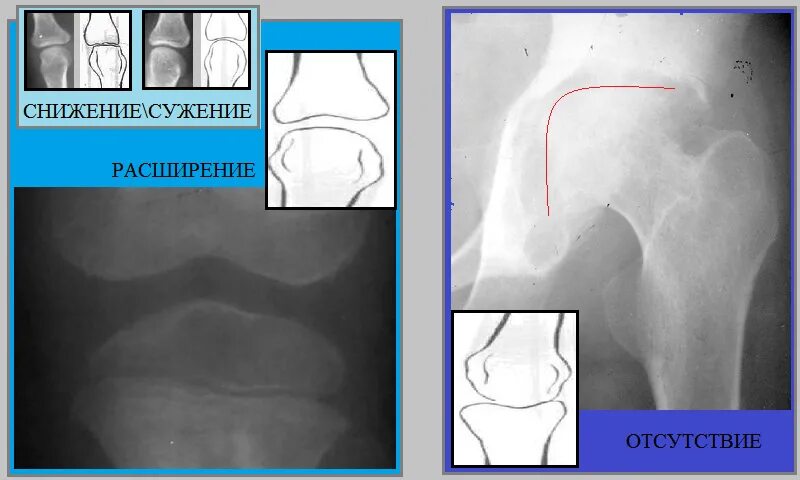

Суставная щель коленного сустава норма